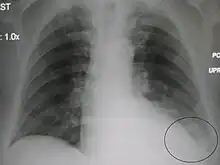

| A parapneumonic effusion (circled), due to a left lower lobe pneumonia. |

A parapneumonic effusion is a type of pleural effusion that arises as a result of a pneumonia, lung abscess, or bronchiectasis.[1] There are three types of parapneumonic effusions: uncomplicated effusions, complicated effusions, and empyema. Uncomplicated effusions generally respond well to appropriate antibiotic treatment.